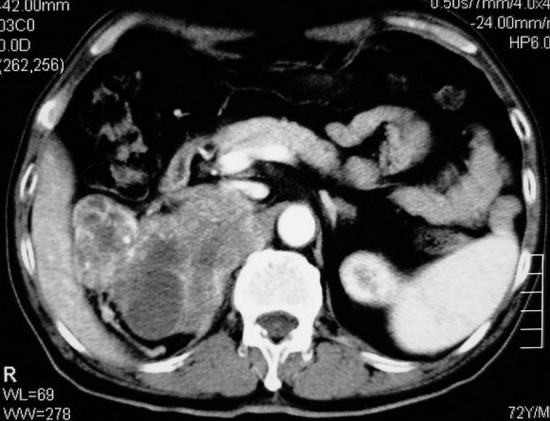

以下是引用杀毒软件在2008-11-17 19:15:00的发言:[br]考虑------右肾癌合并肾静脉---同侧肾上腺受侵可能性大

以下是引用zjzjr在2008-11-17 20:45:00的发言:[br]考虑------右肾癌合并肾静脉---同侧肾上腺受侵可能性大及腹膜后淋巴结转移.